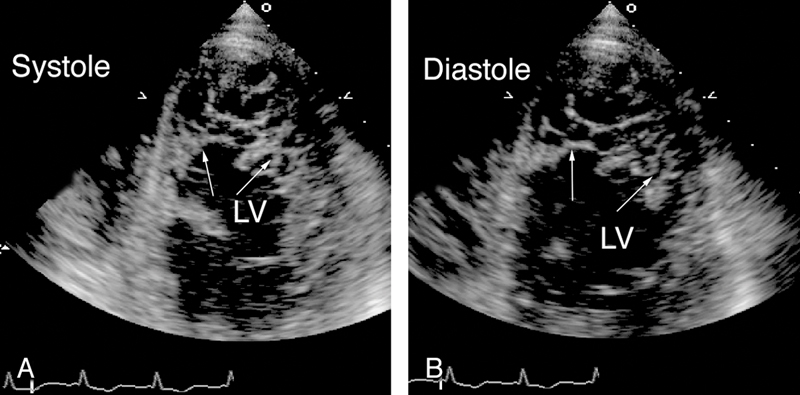

فحوصات تشخيصية لبعض امراض القلب والشرايين التاجية